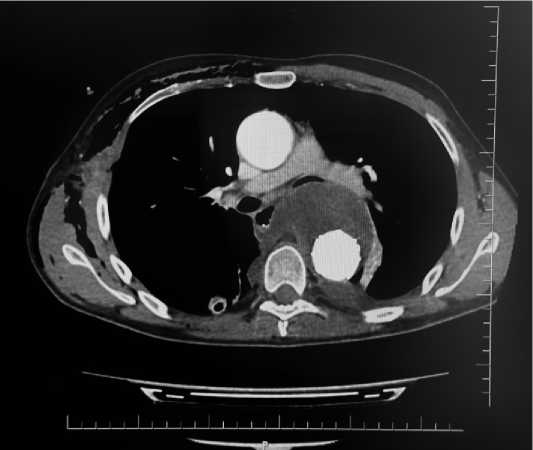

По данным КТ органов грудной клетки: определяется дефект стенки пищевода слева на уровне Th6. В прилегающей клетчатке на данном уровне определяется включение газа, прилегающее к протезу аорты. Лимфоузлы средостения увеличены до 11 мм. Затёка контрастного вещества за пределы аорты не выявлено. Восходящий отдел аорты расширен до 21 мм. Сонно-подключичный шунт проходим. В заднебазальных отделах обоих лёгких определяются фиброзные тяжи. Слева имеется минимальный гидроторакс и повышение плотности лёгочной ткани в S10 с этой же стороны.

Учитывая наличие инфекции протеза (рис. 3) и развития высокого риска протезного кровотечения из аорты, принято решение о проведении оперативного вмешательства.

Рисунок 3. Данные КТ при повторной госпитализации Figure 3. CT data on readmission